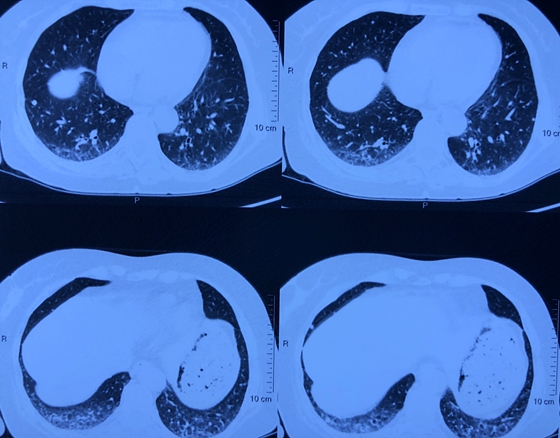

肺部出现间质性改变

游运辉教授带领的团队对聂女士进行了检查,发现:类风湿关节炎很明确,现在是重度活动时期。长时间的不规范治疗,使得聂女士已经出现多个小关节的畸形、功能障碍,肺部也受到累及,发生了间质性改变。关节的畸形不能再恢复,肺部的病变以后也有再进一步进展,出现呼吸困难的可能,目前需要积极治疗。